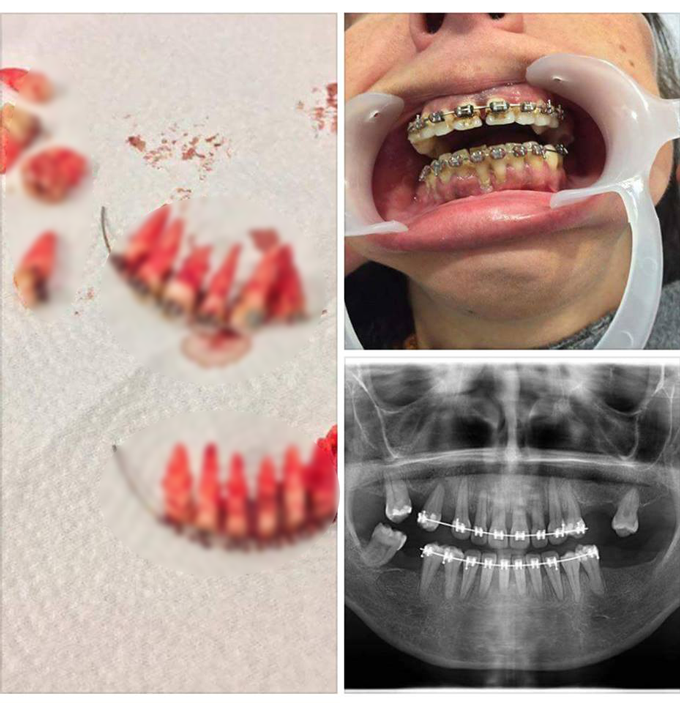

หมอแล็บแพนด้า แชร์ภาพสุดสยอง ผลร้ายของการจัดฟันแฟชั่น หลุดมาทั้งยวง ถอนรากถอนโคน แบบนี้จะกินข้าวยังไงเนี่ย บรึ๋ยยยย...

แค่เห็นก็สยอง จะกินข้าวยังไงน้อ....ส่วนใครที่คิดจะจัดฟัน ควรจัดฟันกับทันตแพทย์ที่มีใบอนุญาตเท่านั้นนะคะ ไม่คุ้มเลยถ้าต้องเสียฟันไปแบบนี้ บรึ๋ยยยยยย...